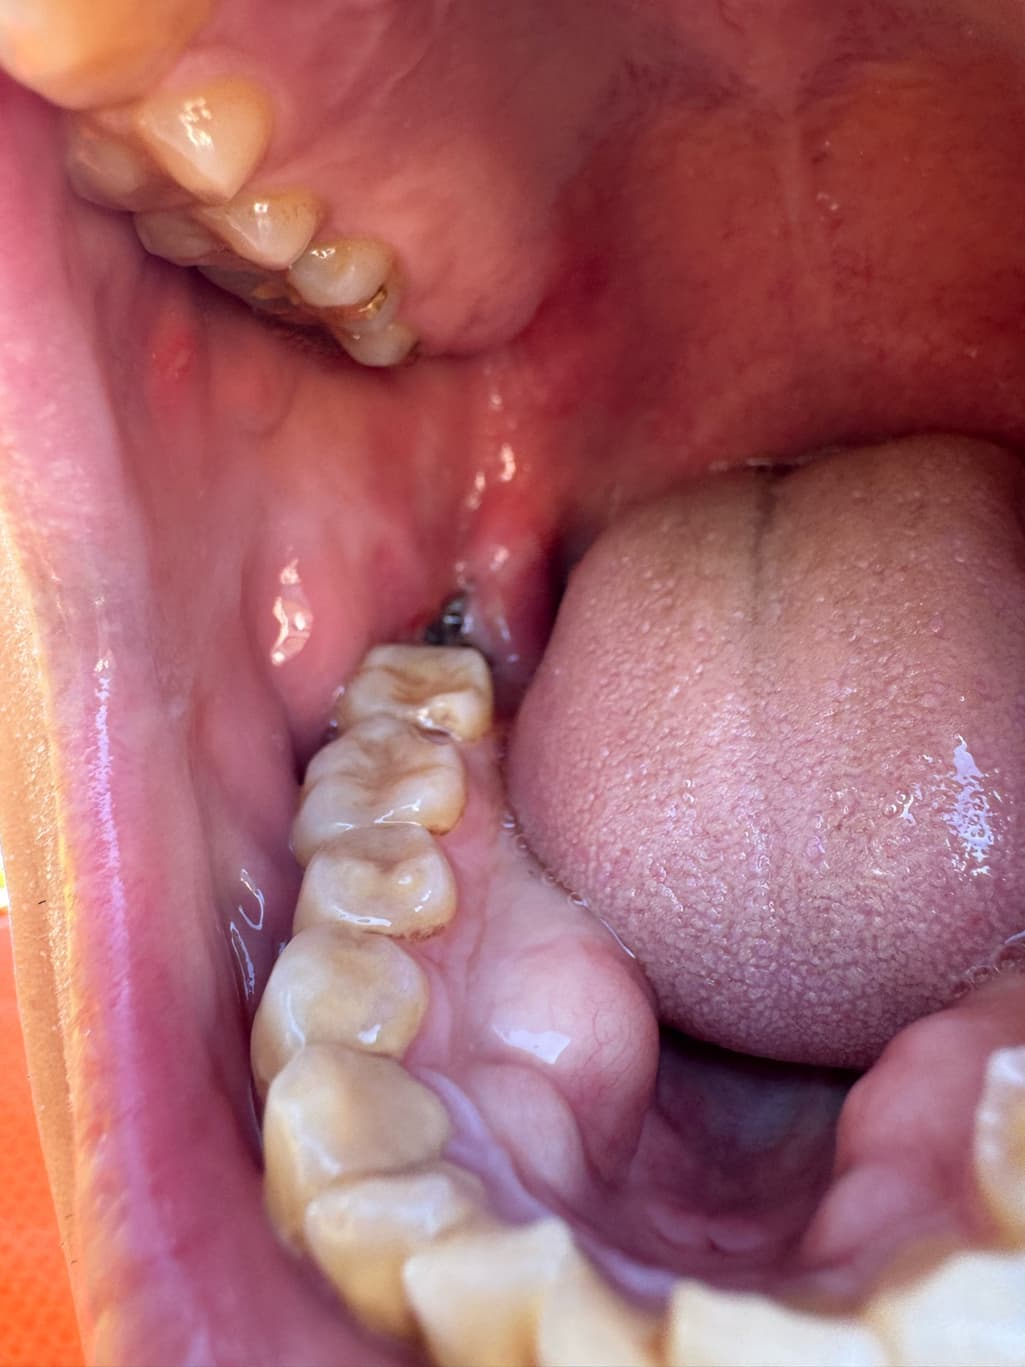

사랑니 발치 후, 이거 제대로 아물고있는게 맞나요

어제 뽑고 하루 지났어요,

제대로 아물고 있는게 맞나요, 혈병 상태도 괜찮은가 궁금하네요, 혹시 제대로 아물고 있는게 맞을까요?

제대로 아물고 있는게 맞나요, 혈병 상태도 괜찮은가 궁금하네요, 혹시 제대로 아물고 있는게 맞을까요? -> 지금으로선 문제 있어보이진 않아요 완전히 아물려면 한달은 있어야 합니다

사진으로 봤을 경우에는 크게 문제가 없이 아물고 있는 것으로 보입니다. 발치한 부위가 잘 아물기 위해서는 자극되지 않는 것이 좋습니다. 대부분의 발치를 한 통증은 3~4일 정도 지나면 없어지게 되며 발치한 부위가 아무는 데는 2주 정도의 시간이 걸리게 됩니다.

사랑니 발치 후 사진상으로는 문제 없이 잘 낫고 있는 것으로 보입니다. 걱정안하셔도 될 듯 합니다.

사진상으로 발치한곳은 잘아물고 잇는거 같으니 자극만 가지 않도록 해주시면될것같습니다.